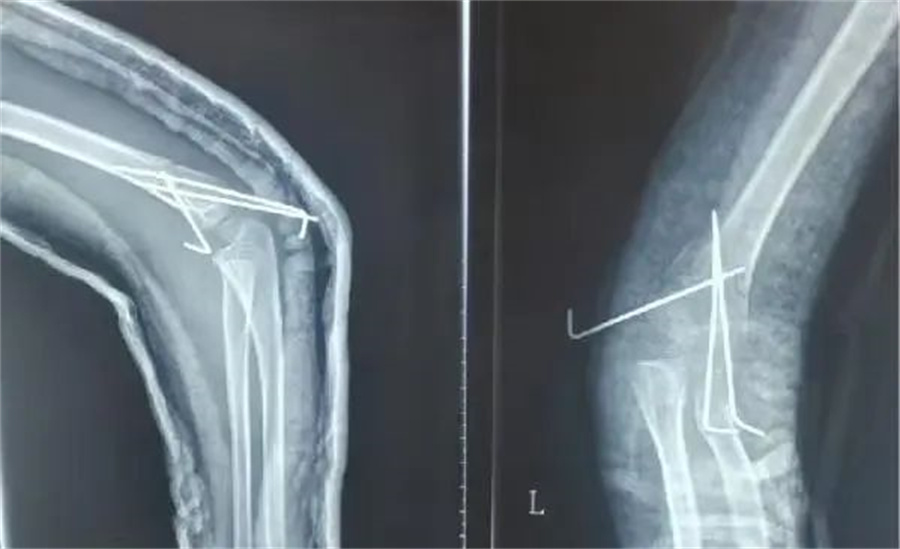

诚瑞的家长赶紧带他来到北京儿童医院集团医院·德州扑克游戏网 。入院当天,骨科医生发现,孩子是重度伸直型三度肱骨髁上骨折。

在各项检查指标都正常的情况下,儿童医院骨科的医护人员为他做了髁上骨折闭合复位术。

正常情况下,这属于常规手术。但是由于诚瑞太胖,胳膊又短又粗,复位的时候摸不到骨头,无形中增加了手术难度。

骨科医生在放射线下,一点一点摸索,最终复位成功,并且术后没有切口,没有瘢痕,4天后,孩子顺利出院。